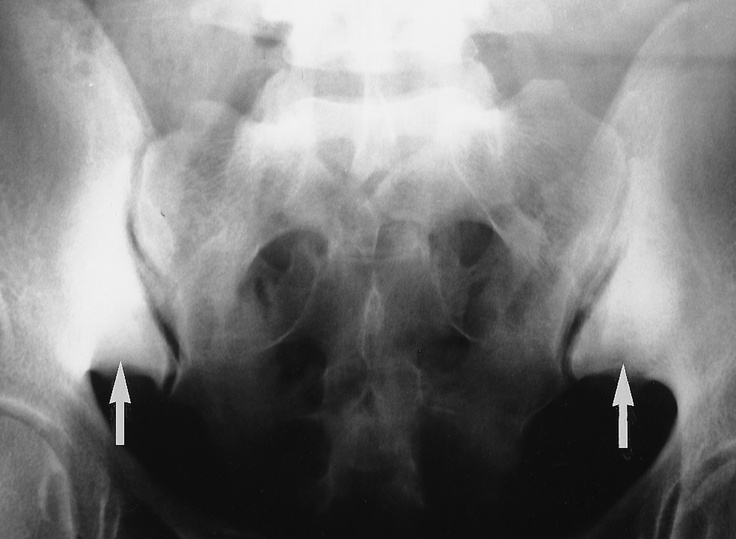

Inflammatory Arthritide: - LBP with morning stiffness - Starts in the SI joints - Males 15-35 yo - Associated with iritis - Bilateral SI joint fusion (ghost joints) - Shiny corner sign (early) in spine - B/L marginal syndesmophytes - Squaring of the VB’s - Bamboo Spine - Dagger Sign - Trolley Track sign - Poker spine

Ankylosing Spondylitis